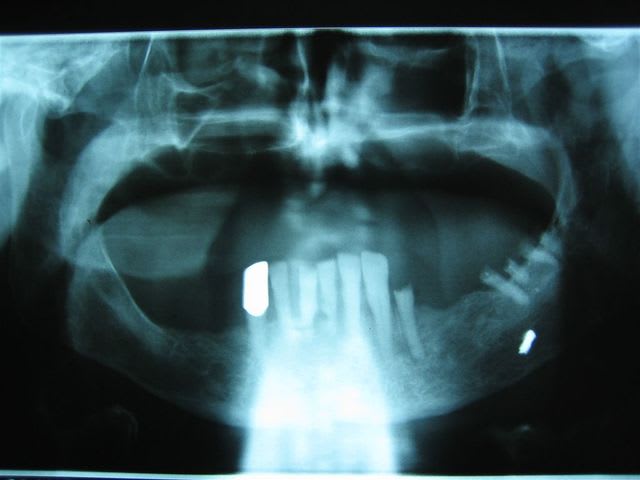

Bonjour

Que peuvent etre ces images de calcification ?

Cela me semble un peu bas pour la parotide et un peu haut pour la sous-max

Calcifi ia5hkz - Eugenol

... artério-sclérose carotidienne?

Je pensais aussi à ca : faut il l'adresser a son cardio ?